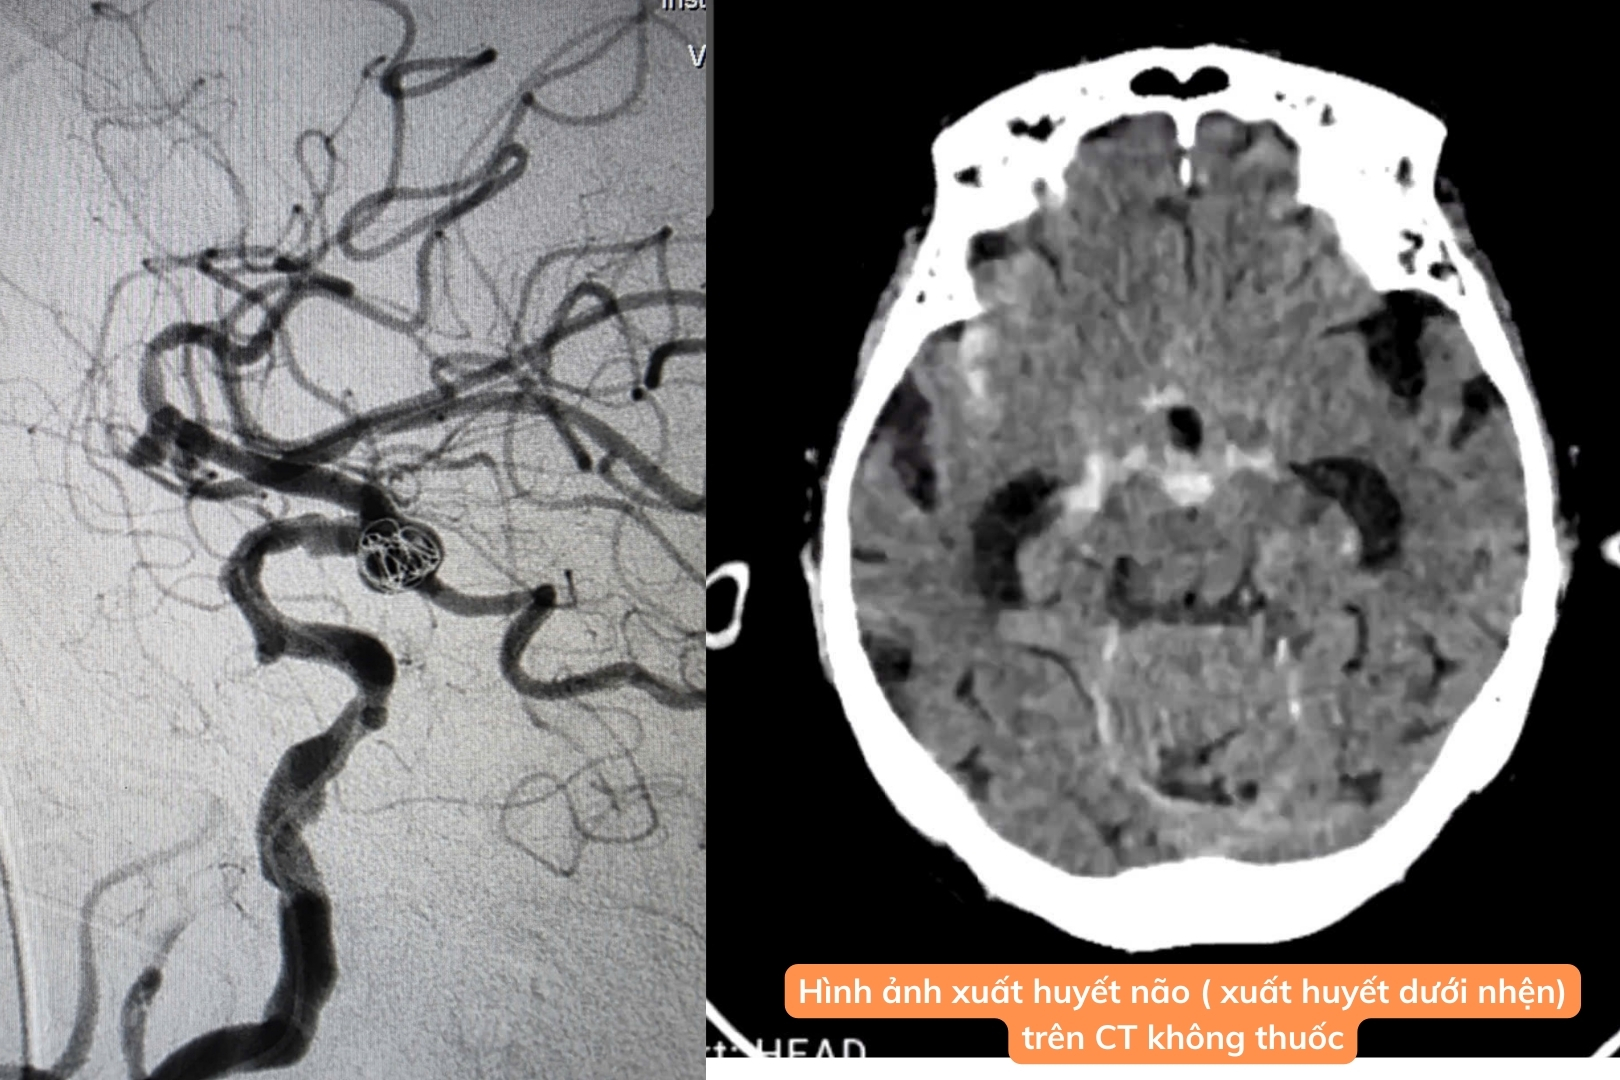

Đêm 19/8/2025, các bác sĩ Bệnh viện Đa khoa Châu Đốc (An Giang) đã kịp thời can thiệp cấp cứu cho một bệnh nhân 79 tuổi bị vỡ túi phình mạch máu não gây xuất huyết dưới nhện. Chỉ sau 45 phút, ca bít coil túi phình đã hoàn tất, giúp bệnh nhân qua cơn nguy kịch và tỉnh táo trở lại vào sáng hôm sau.

Khuya 19/8/2025, cụ bà 79 tuổi nhập viện trong tình trạng đau đầu dữ dội, có tiền sử tăng huyết áp. Ngay lập tức, ekip khoa Nội Thần kinh – Đột quỵ tiến hành chụp CT não và CTA mạch máu não, phát hiện xuất huyết dưới nhện do túi phình động mạch não đoạn C7 kích thước 3×5×5 mm vỡ.

Nhận thấy tình trạng nguy cấp, ekip can thiệp lập tức được kích hoạt. Trong vòng 45 phút, các bác sĩ đã bít coil túi phình thành công, ngăn chặn nguy cơ xuất huyết tái phát, đồng thời bảo tồn tối đa chức năng não bộ cho bệnh nhân.

Sau can thiệp, bệnh nhân tỉnh táo, giảm đau đầu rõ rệt (Ảnh: BSCC)